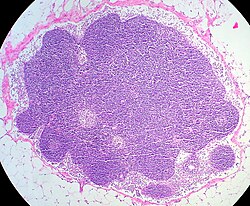

1 Kapsel, 2 Randsinus

3 Sekundärfollikel

4 Parafollikulärer Raum

5 Trabekel

Ein Lymphknoten ist von einer Kapsel umgeben, von der Bindegewebssepten (Trabekel) ins Innere ziehen. Das funktionelle Gewebe im Inneren ist ein lymphoretikuläres Gewebe. Es besteht aus Retikulumzellen und freien Zellen (Lymphozyten, antigenpräsentierende Zellen). Das lymphoretikuläre Gewebe des Lymphknotens ist in drei Gebiete gegliedert, in denen die Lymphozyten an körperfremden Eiweißen immunologisch „reifen“:

- In der Rinde (Cortex nodi lymphoidei) sind die Lymphozyten zu Rindenfollikeln (Lymphknötchen) organisiert. Sie dienen der Vermehrung und Differenzierung der B-Lymphozyten.

- Im Mark (Medulla) ist das lymphoretikuläre Gewebe in Strängen gelagert.

- Zwischen Rinde und Mark liegt eine Übergangszone (Paracortex). Dort findet die Vermehrung der T-Lymphozyten statt.

Die Retikulumzellen bilden im Lymphknoten ein dreidimensionales Maschenwerk, dessen Hohlräume als Sinus lymphaticus bezeichnet werden. Dieser wird in den unter der Kapsel liegenden Randsinus, den im Bereich des Marks befindlichen Marksinus (Syn. Medullarsinus) und den dazwischenliegenden Intermediärsinus untergliedert.